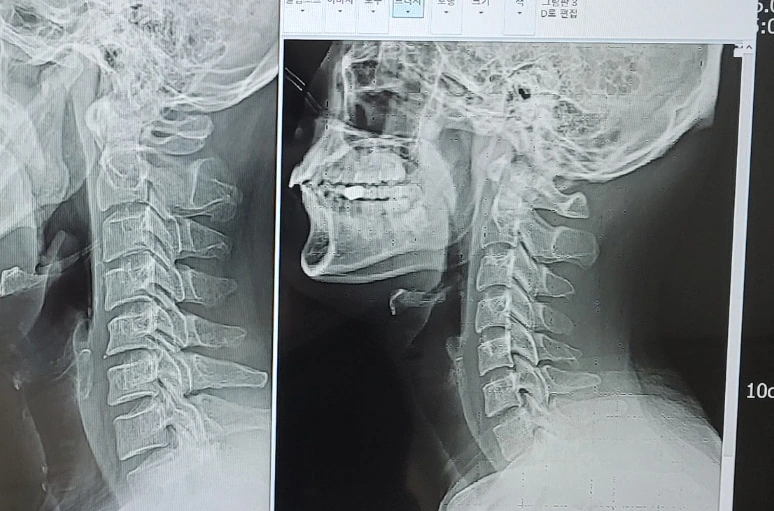

엑스레이를 찍고 다시 의사와 마주 앉았다. 입안은 바짝 마르고, 손끝이 조금 떨렸다. 그 뼈다귀가 선명하게 그려진 사진을 보며, 나는 의사의 얼굴을 예의주시했다. 그가 무표정하게 화면을 들여다보는 몇 초가 몇 분처럼 느껴졌다.

"음… 목이 일자 목이시네요."

난 의아했다. 내가 일자목이라고. 사실 이런 증상이 처음이었기 때문에 목과 어깨에 엑스레이를 찍어 보질 않았으니 전혀 모르고 있던 사실이었다. 50년을 살면서 처음 들었던 일자목이라는 그 한마디에, 나를 조여오던 수많은 상상이 순간적으로 무너졌다.

"최근에 고개를 너무 숙이고 계셨나요? 일자목이 신데 높은 의자에 앉아 모니터를 내려 보거나, 혹시 책을 너무 아래에 놓고 보시거나 해서 목뼈가 자극을 받아서 어깨 신경을 건드린 것 같네요."

그는 내게 정상적인 목뼈 사진과 내 목뼈 사진을 나란히 보여주며 말했다.

"이거 사진 한 장 찍어가시고요. 앞으로는 목을 이렇게 유지해주셔야 합니다."

모든 공포가 허탈하게 풀리는 순간이었다. 이미 원인을 의사가 말했지 않은가? 책을 많이 보고 모니터를 내려다보아서 그런 것이라고…